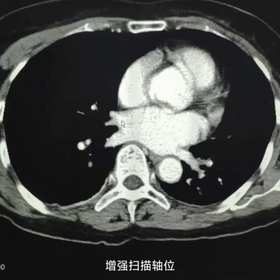

63岁女性患者,因右踝关节骨折住入我院骨伤科,无反复呼吸道感染及咯血病史,无咳嗽、胸痛、消瘦、乏力。入院后常规拍胸片意外发现左下肺心影后团块状高密度影,进一步行胸部CT示左肺下叶基底段团块状软组织密度影,形态不规则,有浅分叶,不除外肿瘤,建议CT引导下肺穿刺活检。内四科姚纲副主任医师会诊后建议行胸部CT增强扫描,用我院64排128层西门子螺旋CT增强扫描示病灶中度强化,三维重建示左下肺病灶由后肋间动脉供血,诊断为肺隔离症(叶内型)。

轴位增强扫描